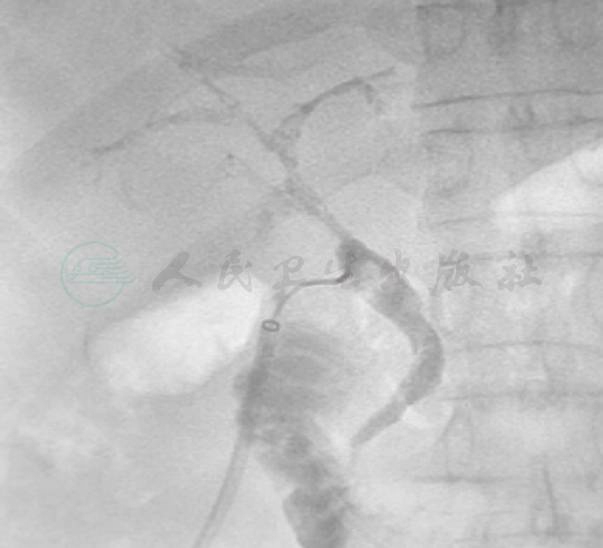

影像学检查:T形管造影:肝总管及肝内胆管条索状负影,肝内胆管分支不显影(图1)。

图1 肝移植后8周的T形管造影